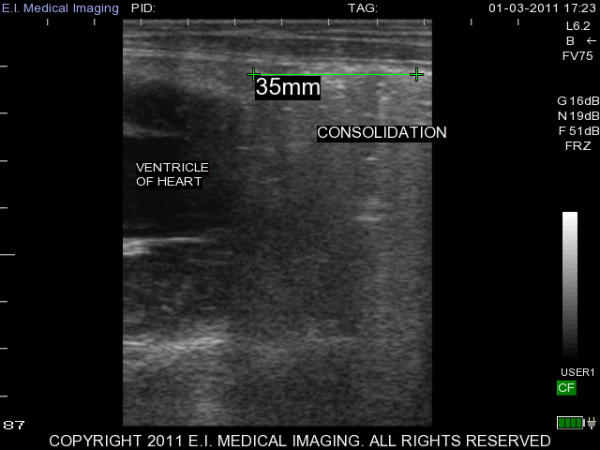

My name is Elizabeth Adams and I am a dairy practitioner in the central valley of California. Recently, I was able to use the IBEX PRO portable ultrasound to look at calf lungs for evidence of damage from calfhood pneumonia. In veterinary school, I scanned all of my patients with respiratory symptoms because it is a fast, non-invasive exam that provides a lot of information quickly. With ultrasound I can see healthy lungs, pleural effusion, atelectasis, consolidation and abscessation.

Ultrasound allows me to look at the surface of the lung; in a healthy lung, this is all we can see as the lung is full of air and doing its job. In a diseased lung, the surface of the lung is abnormal and allows penetration of the ultrasound waves deep into the lung parenchyma. Young calves require only the penetration of a 5-7.5MHz rectal ultrasound probe to see the evidence of damage from previous pneumonia.